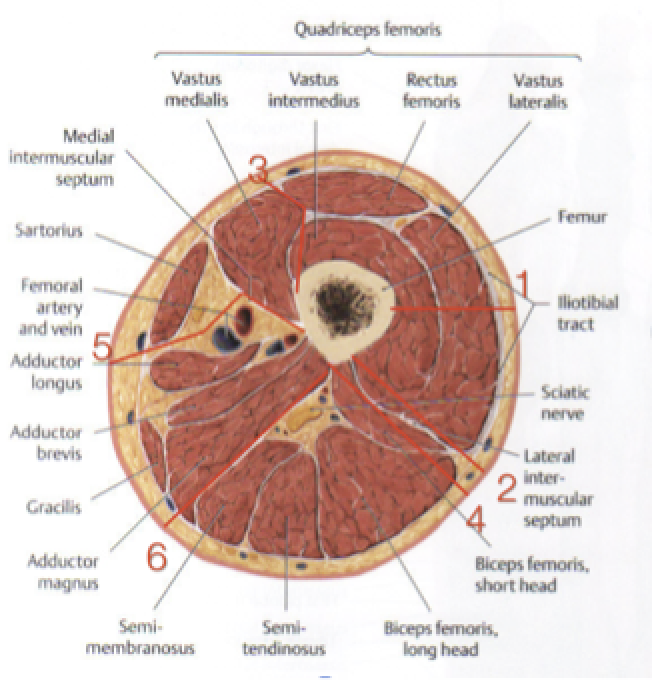

Posterior Approach to the Femur

Interval: Lateral Intermuscular Septum & Biceps Femoris (Tibial Branch of Sciatic N.)

Approach:

- Midline incision over posterior femur.

- Find septum, retract biceps laterally to expose sciatic N.

- Incise the short head of biceps femoris at the linea aspera, and retract it laterally to protect Sciatic N. and expose femur.

Dangers:

- Sciatic N

- N. to biceps femoris

- Posterior Femoral Cutaneous N. (PFCN)

(#4 on diagram)